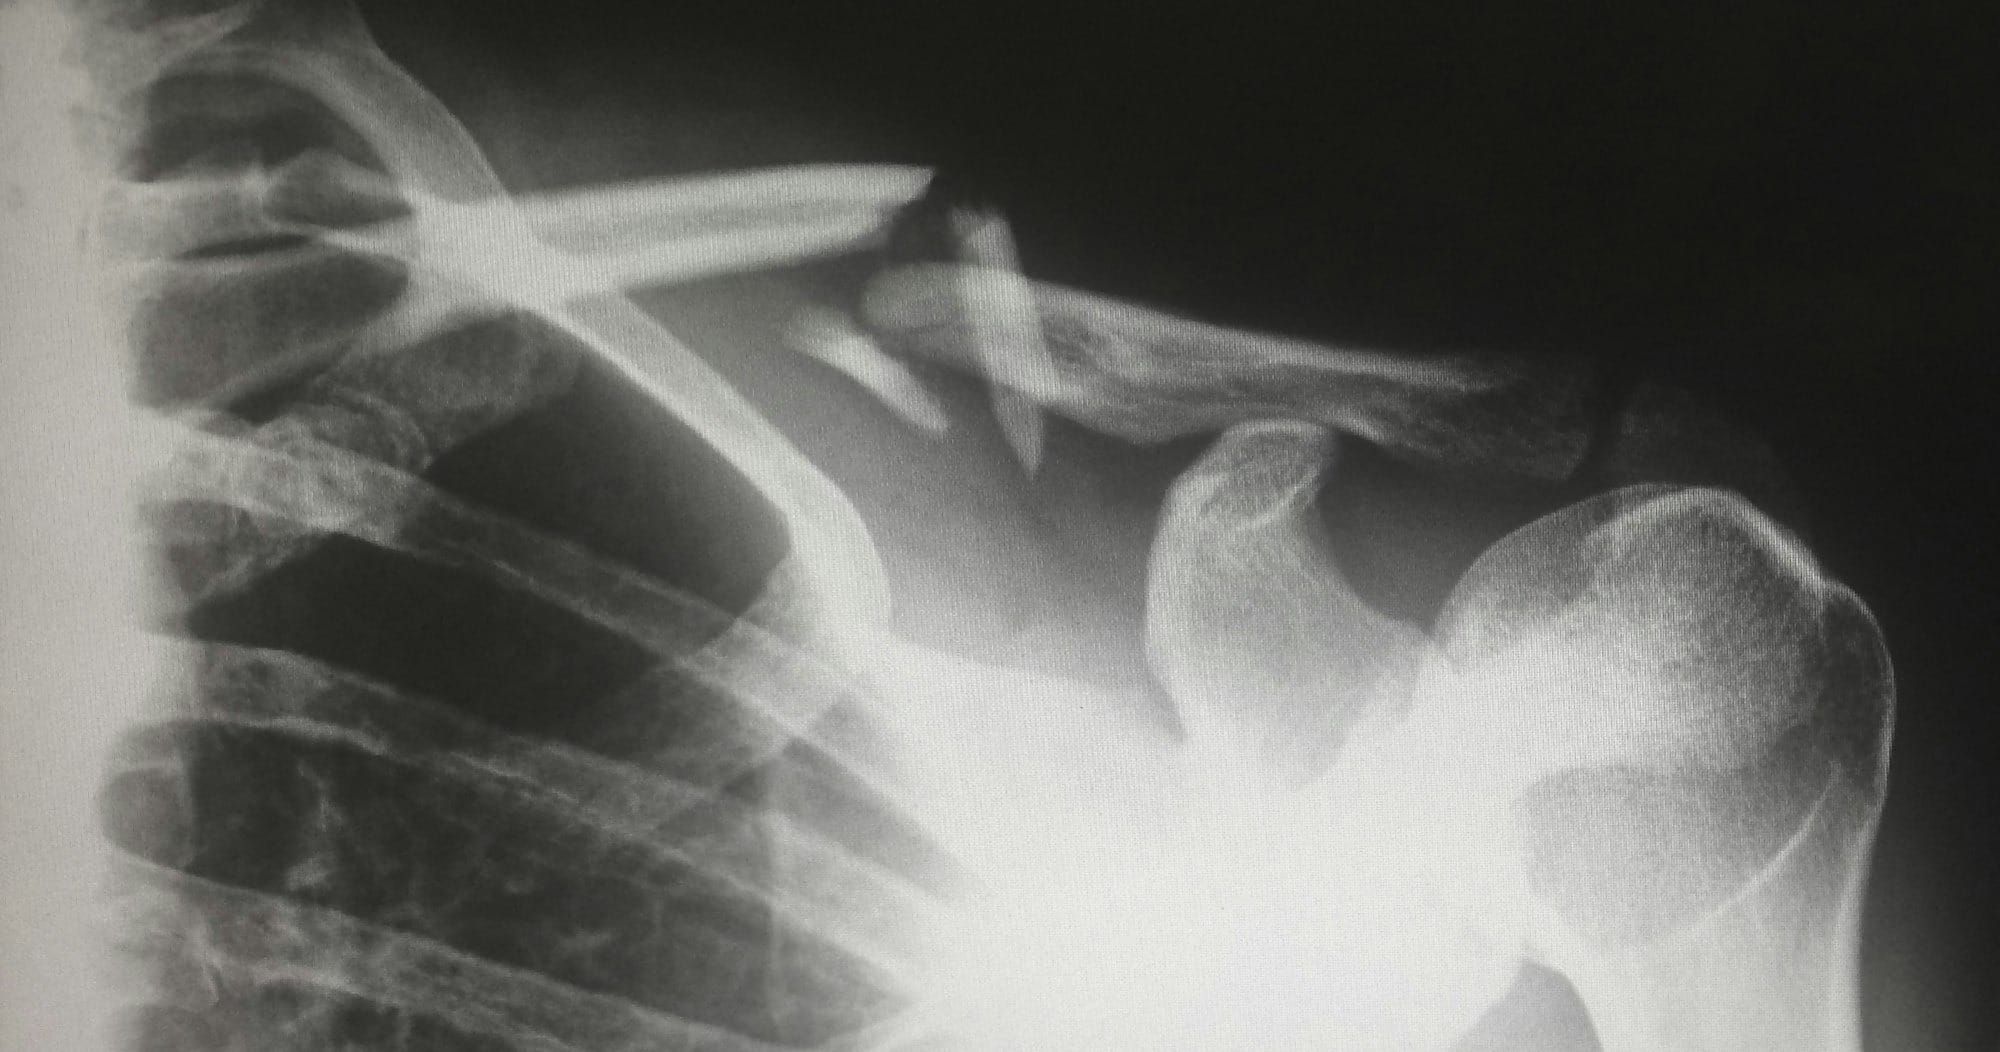

Photo by Harlie Raethel / Unsplash